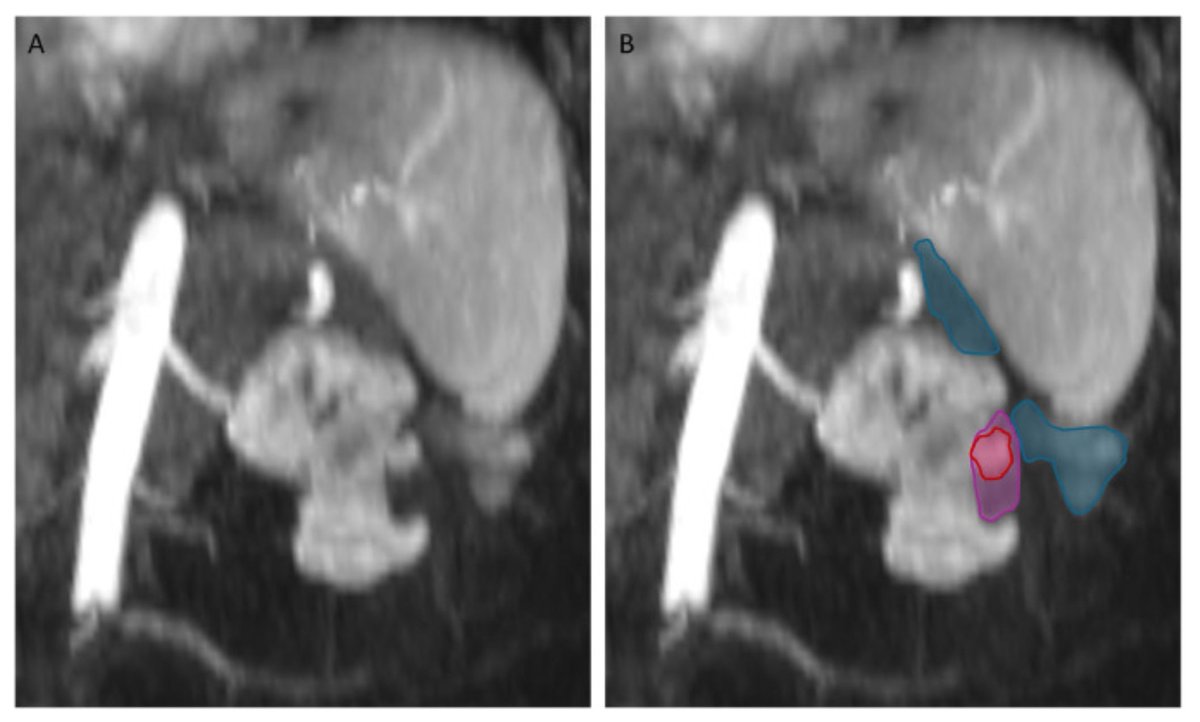

Interventional Radiology has a leading responsibility for patients with #HCC.

Congrats to my colleague @FZIslamMD for leading our latest pub, which highlights the importance of multidisciplinary management for HCC + the critical footprint of Interventional Radiology across multiple timepoints. 📝 dovepress.com/real-world-ana… @BeauToskichMD @MayoClinicFL_IR